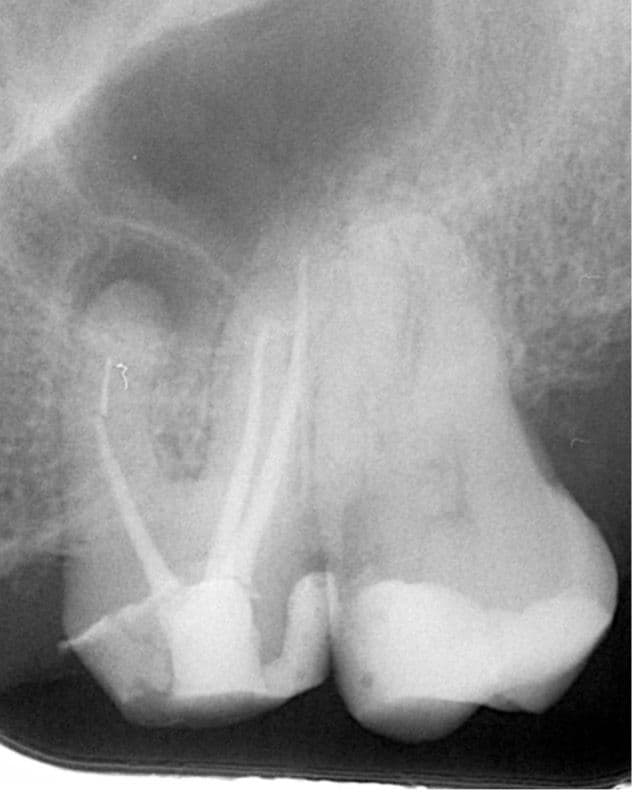

Kontrolden 14 ay sonra (2025 Nisan) hastamız bu sefer 26 numaralı dişinde ağrı şikayeti ile kliniğimize başvurdu İlgili dişe sonunda retreatmant tedavisine başlanabildi. (Şekil 4).

(Şekil 4) 2025 Nisan meziobukkal kök ucunda daha da genişlemiş periapikal lezyon